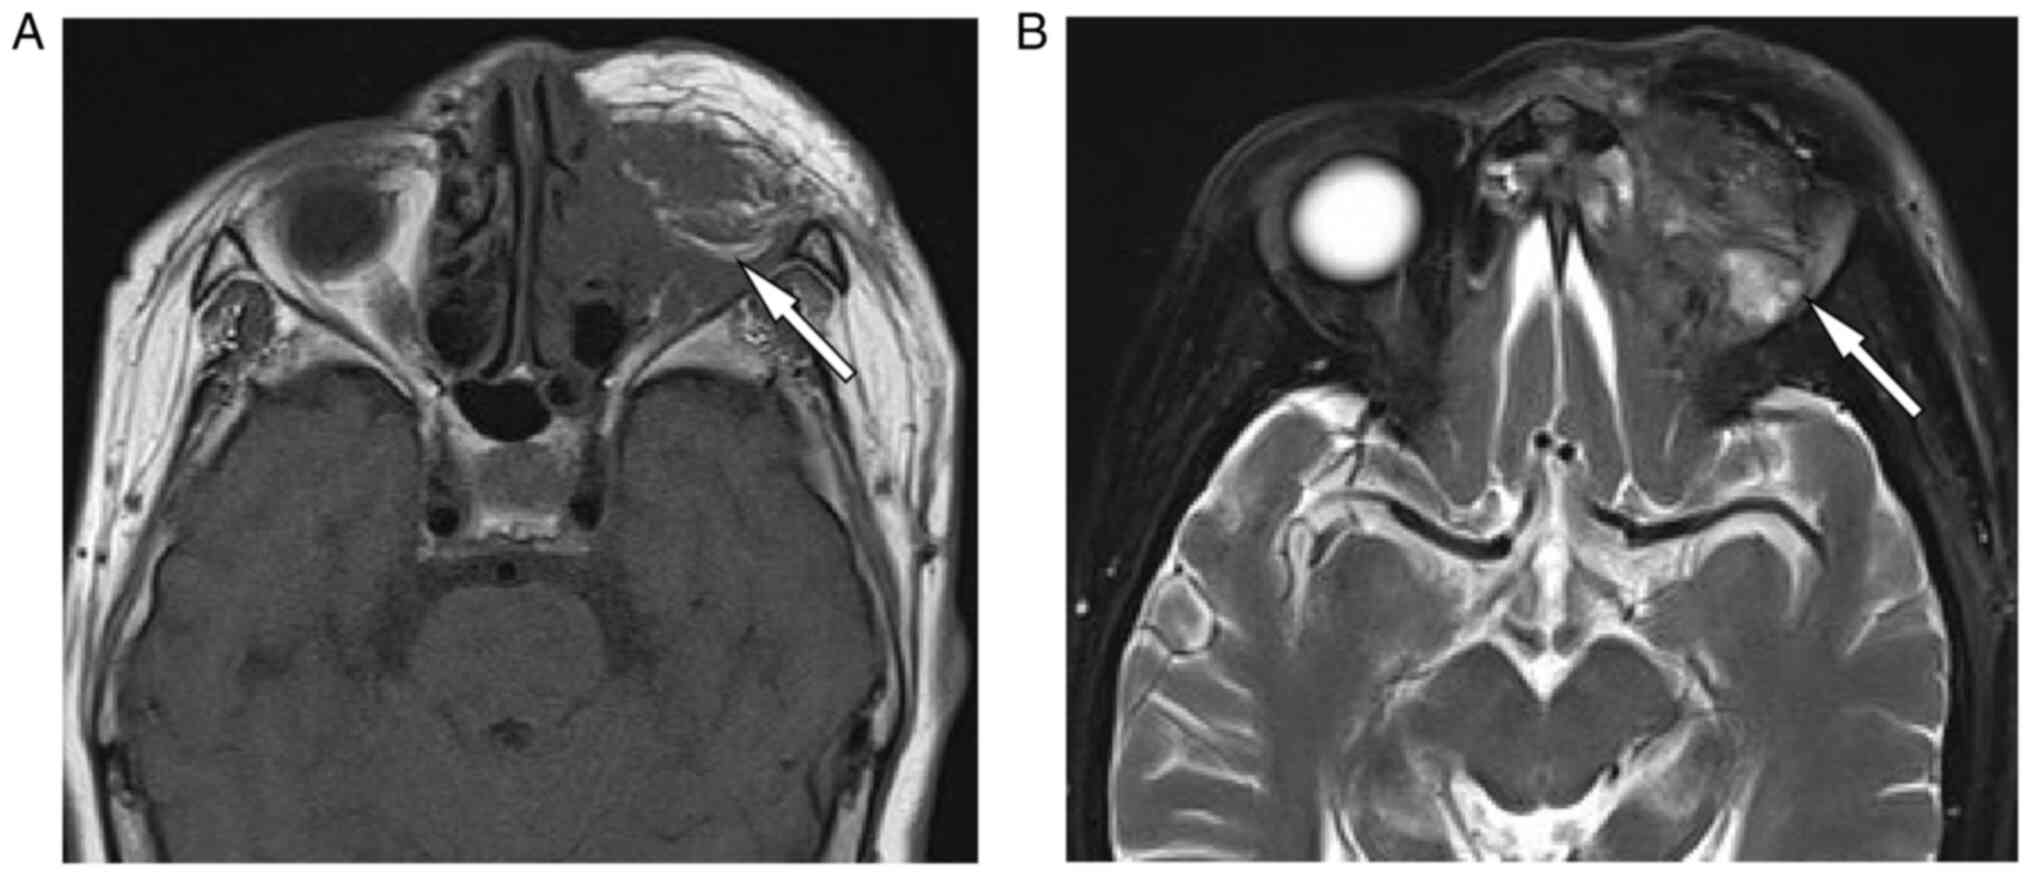

Figure 4.

Magnetic resonance imaging at 7 months and 1 week after surgery, which showed a postoperative absence of the left eyeball, and a heterogeneous lump presenting with (A) a slightly hypointense signal on T1WI and (B) a slightly hyperintense signal on T2WI in the operative area, suggesting tumor recurrence. WI, weighted imaging.